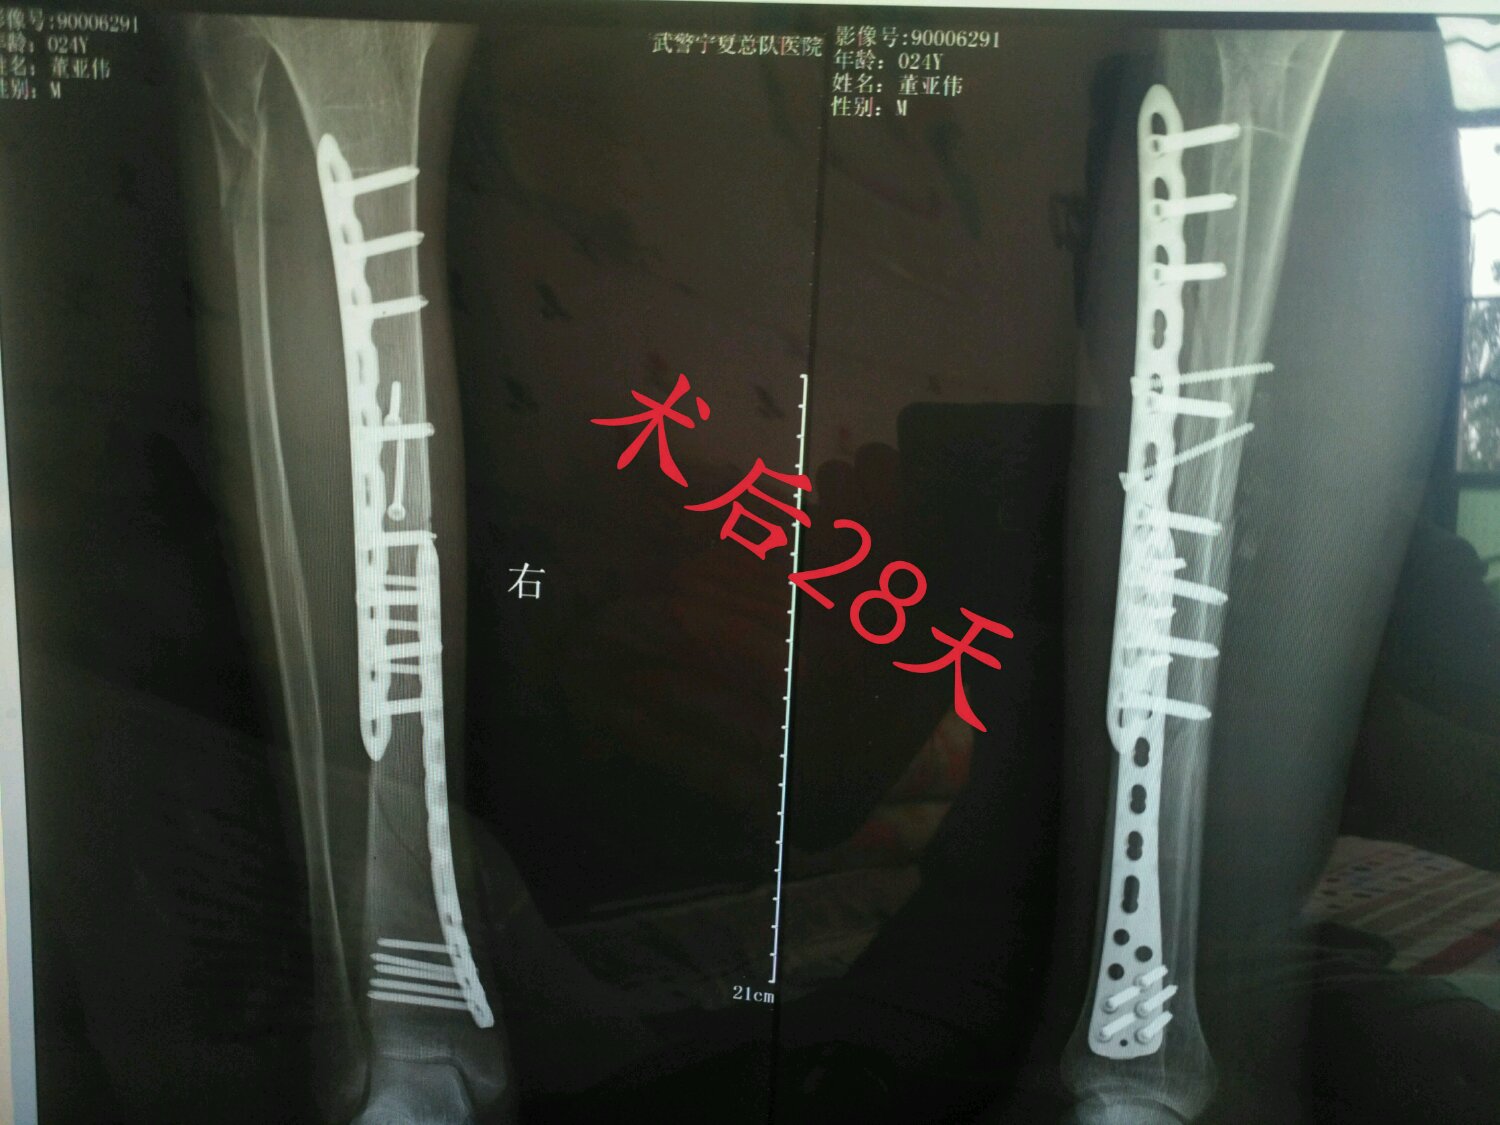

帮我看下这个骨头长了没有?谢谢

额不到一个月??我90天还看不出来。。别着急了。会好的相信

小腿是长的最慢的地方,一般三个月才会看到长

回复 天蝎男℃ :下地走路恢复好的话四个月左右,恢复跟以前一样走再加两个月